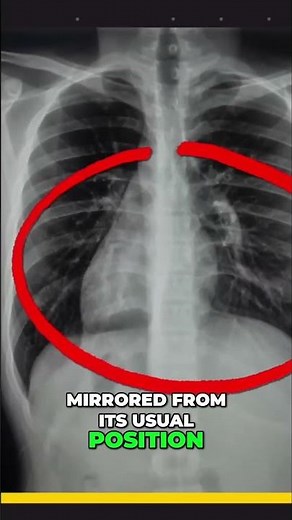

- Dextrocardia vs

Situs Inversus - Hitman

Coarctation - Situs Inversus

Atrium - Situs Inversus

Echo - Dextrocardia Situs Inversus

Solitus - Situs Inversus

Eye - Dextrocardia with Situs

Inversus.stress Test.echocardiogram - Hitman Situs Inversus